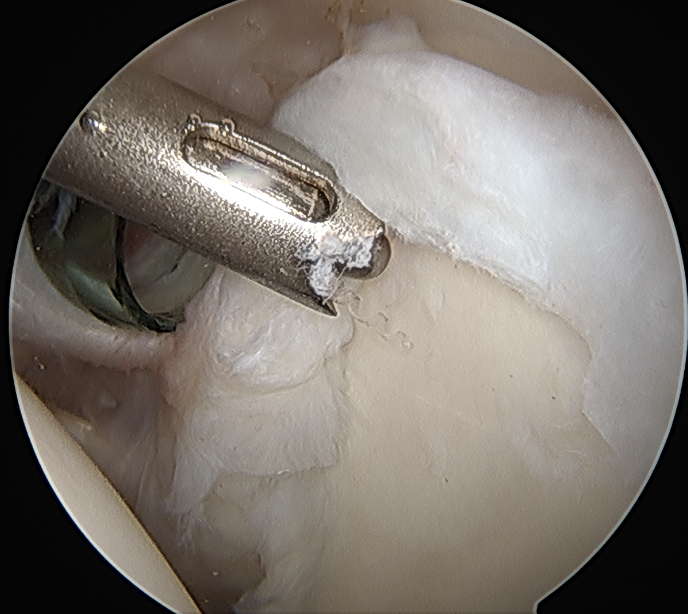

Arthroscopic SLAP repair

Technique

Beachchair

- anterior portal for suture passage / superior glenoid debridement

- lateral portal to insert anchors

- anterior to supraspinatus tendon / portal of Wilminton (posterior infraspinatus transrotator cuff)

- debride superior glenoid to bleeding bone

- anchor repair

Trans-rotator cuff portal and portal anterior to leading edge supraspinatus